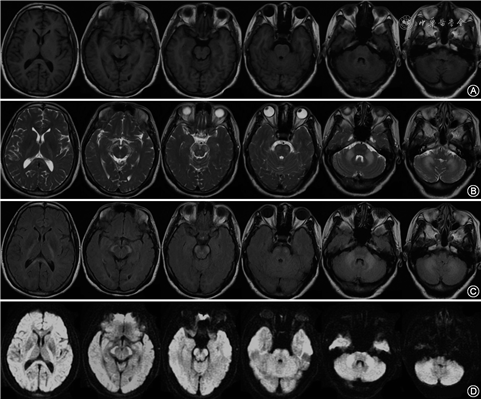

患者女性,48岁,以“发作性头痛10年余,行走不稳7年余”于2020年6月25日就诊于复旦大学附属华山医院。患者于2010年无明显诱因出现发作性头痛,主要表现为顶、枕部胀痛,伴恶心,无畏光和呕吐,一般休息2~3 d后好转,每年发作3~5次。2013年起患者开始出现行走不稳伴头晕和记忆力减退,稍复杂的家务完成有困难。症状呈进行性加重,无言语不清,无肢体麻木无力,无脚踩棉花感等表现。患者既往史无特殊,否认家族史和父母近亲婚配史。其父亲因“食管癌”在50岁时去世。神经系统体检:意识清楚,近记忆力、计算力、执行能力下降;简易精神状态检查量表评分为24分,蒙特利尔认知评估量表评分为18分。脑神经检查未见明显异常,四肢肌力Ⅴ肌,肌张力正常,四肢腱反射亢进(+++),双侧Babinski征(+);双侧深浅感觉对称无明显异常,双侧指鼻试验、跟膝胫试验欠稳准,一字步困难。入院后辅助检查:血常规:血红蛋白104 g/L(正常值115~150 g/L),肝肾功能、糖化血红蛋白、甲状腺功能、维生素B12、叶酸、同型半胱氨酸、梅毒血清学试验、HIV抗体、抗核抗体和肿瘤标志物均正常;2020年6月8日,患者行头颅MRI(图1)提示双侧内囊后肢、大脑脚、脑桥、小脑中脚及小脑对称性异常信号,T1WI呈低信号,T2WI、T2 FLAIR和DWI呈高信号。磁敏感加权成像(susceptibility weighted imaging)未见明显异常,磁共振波谱分析(magnetic resonance spectroscopy,MRS)提示N-乙酰天冬氨酸(N acetyl aspartic acid,NAA)峰未见明显降低,胆碱峰未见明显升高,胆碱/NAA比值在正常范围内。脑电图正常。

LKPAT特征性的MRI改变为双侧内囊后肢、大脑脚、小脑中脚的对称性的信号异常,T1WI低信号,T2WI、T2FLAIR及DWI高信号;也可累及脑桥锥体束、小脑上脚、胼胝体及其他大脑与小脑的白质,而脑室旁白质多不受累[1]。弥散张量纤维束成像可发现锥体束、桥横纤维和小脑齿状核纤维明显变薄[1]。该MRI改变具有显著特征性,是支持诊断的重要临床线索。Depienne等[6]认为CLCN2基因功能丧失导致脑组织水电失衡,引起渗透性髓鞘内水肿,是出现这种特征性MRI改变的重要原因。本例患者头颅MRI所示病变分布、范围以及不同序列的成像特点与既往报道相符。此外,我们还对本例患者进行了MRS检查,未发现NAA峰、胆碱峰及胆碱/NAA比值的异常,有待未来在更多的患者中进一步验证。